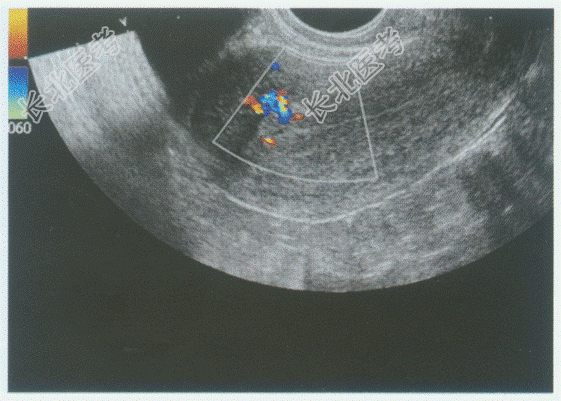

- 单项选择题临床资料:女性患者, 23岁,自述药流术后19天, 阴道出血。

超声综合描述:子宫形态饱满, 宫腔内见1.1cm×0.8cm中强回声区,边界不清晰, 内回声不均,CDFI: 内可见血流信号。见下图及彩图。